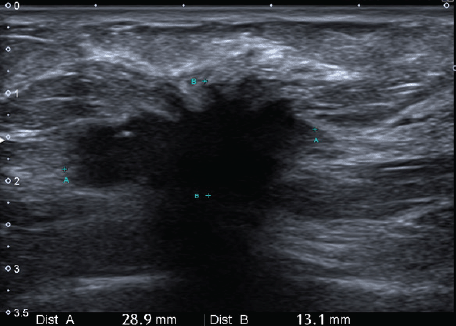

We present the case of a 36-year-old woman, with insulin resistance, without a family history of breast cancer, who consulted for a 6-month evolution self-detected left breast nodule associated with skin retraction. At the physical exam, there was a 20-mm palpable mass retracting the skin at the lower-inner quadrant (LIQ) of the left breast, without clinically evident axillary adenopathies. The patient was studied with mammography [Figure 1] and breast ultrasound [Figure 2], which showed a spiculated mass of 29 × 24 × 14 mm at the LIQ of left breast, with the increased flow at doppler, diagnosed as BIRADS-5. A core biopsy was performed, demonstrating a poorly differentiated invasive ductal carcinoma with positive oestrogen receptor (99%; / ), positive progesterone receptor (90%; ), positive human epidermal growth factor receptor type 2 (HER2) 3 , fluorescence in situ hybridisation for HER2 and Ki-67 30%. The staging study demonstrated an osteolytic lesion compatible with sternal metastasis evident in computed tomography (CT), positron emission tomography (PET)/CT and magnetic resonance imaging (MRI) [Figure 3]. The staging was completed with sentinel lymph node biopsy, obtaining six lymph nodes without metastasis. The primary lesion was marked with two metallic clips guided by ultrasound. The patient completed neoadjuvant ST with Doxorubicin, Cyclophosphamide, Paclitaxel, and HER2-directed therapy with Trastuzumab and Pertuzumab, with a complete clinical response at physical exam and images [Figure 4]. Later, she underwent left partial mastectomy, using percutaneous hookwire for the location of the metallic marker clips. The definitive biopsy demonstrated an area of 27 × 25 × 15 mm of scarring substitutive fibrosis associated with isolated microfocus (less than 1 mm) of moderately differentiated invasive ductal carcinoma with negative margins. The study of residual tumour load reported 1% invasive carcinoma and 0% intraductal carcinoma in situ. Two months after the surgery, LT with radiotherapy was completed. The breast was treated with tangential X-ray fields of 6 and 18 MV, the supraclavicular and left axillary region with a right anterior oblique field, and the internal mammary territory and sternum with an array of photons of 18 MV and electrons of 9 MeV, completing in all areas a dose of 50 Gy in 25 fractions in 5 weeks and then a boost of 10 Gy in 5 fractions over the tumour bed. Subsequently, it was decided to complete ST with Trastuzumab and Pertuzumab, in addition to pharmacological ovarian suppression with Triptorelin plus Tamoxifen. The HER2-directed therapy will be maintained until the progression of the disease or toxicity.

Figure 2. Ultrasonic left breast showing a hypoechogenic-spiculated mass with the acoustic shadow of 29 × 24 × 14 mm3 in correspondence with the mammographic image.